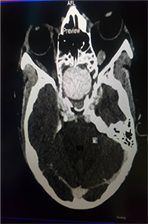

A cranio-cerebral CT scan with injection of contrast product found a rounded mass at the level of the sphenoid sinus, measuring 30 × 27 × 22 mm (9.26 cc) This mass was strongly enhanced after injection of contrast product, communicating with the left ICA at level of its cavernous part. There was a mass effect on the left superior orbital fissure with an increase in the size of the left ophthalmic artery. Furthermore, we noted grade II exophthalmos and left frontal cortico-subcortical hypodensity and discontinuity of the ethmoid cells and the lateral wall of the sphenoid sinus, probably residual. At finally, we have concluded to a left carotid-cavernous fistula on aneurysm, type A according to the angiographic classification of Barrow et al. (Figure 1).

(a) (b) (c)

Figure 1. Craniocerebral CT scan of the patient (a): Axial section through the orbital apexes. Grade II exophthalmos (b) and (c): Sagittal sections. Contrast, bone lysis.